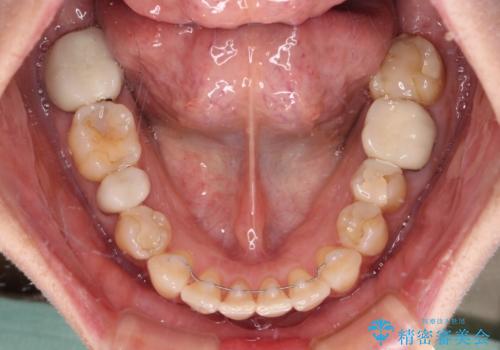

- 矯正装置

- 審美装置

- 前歯のデコボコを気にして来院された患者様です。

舌突出癖により、上下前歯がなかなか接触せずに治療期間を要しましたが、舌のトレーニングにより無事に治療を終えることができました。